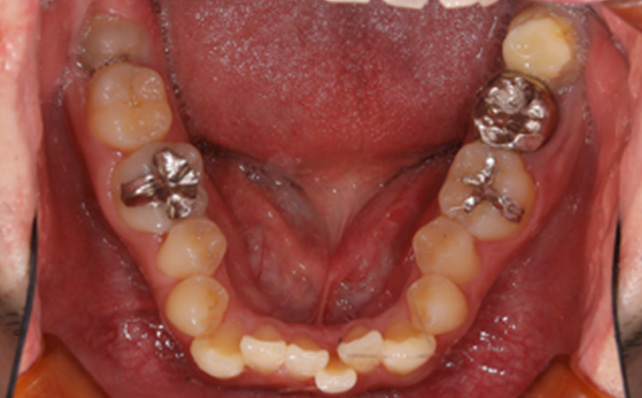

治療後

治療で得られるメリット ・叢生が治ると日々のメンテナンス(ブラッシング)がしやすくなるため、汚れがたまりにくくなります。

・そのため虫歯や歯周病になりにくく、将来的に自分の歯を健康な状態で保ちやすいです。